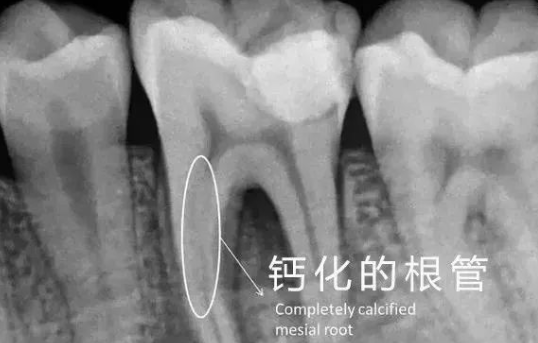

根管治疗术的过程是医生用根管治疗专用器械通过彻底去除感染的牙髓以及感染的牙本质和毒性分解产物,经过根管冲洗、消毒和严密填塞根管,隔绝细菌进入根管再感染,防止根尖周病变的发生或促进根尖周病的愈合。根管预备前的思想准备包括:要预知根管多少、走向、形态(排除法、X片、探查);要想到采用的预备步骤(步退、冠向下);要想到最终预备形态;要充分认知和选用器械。在根管治疗之前,除了要有以上准备外,操作前还要进行操作前评估,患者是初次还是再次治疗、评估难度、操作程序及器械的选择、进入根管是否困难、是否存在冠部修复体、根管桩、根管弯曲、根管过长、根管钙化、牙齿扭转和倾斜、既往不良根管治疗的情况、残留外来物、根管治疗材料等。

原则的遵守包括:a、 操作前评估根管的解剖形态(术前多角度X片的拍摄)提供更可靠的根管形态信息。b、保持根尖开放、防止碎屑等堵塞根尖孔是提高根管治疗效果的关键点、一旦确认长度后,在根管预备中总是保持疏通这一操作步骤)冲洗、15#K锉是基本通路。c、充分有效的冲洗;建议冲洗液总量为75---150ML、5.25%的次氯酸钠、洗必太(杀菌)和SmearClear(清除玷污层,是根管预备的最后步骤)。d、使用冠向下预备概念;冠1/3、中1/3、下1/3。最易清除玷污物、减少器械分离的可能。e、操作使用器械;半被动式概念,探查前行,感觉正向阻力(警惕)和侧向阻力(放心)。当遇正向阻力时不可强行用力,选择稍大的器械(在阻力上方)、稍小的器械(在侧方、下方)开辟空间寻原始通路。f、通路和塑形;手用扩大针(ISO)用于寻找和疏通通路,大锥度器械(镊钛手动、机动)用于根管的塑形。g、正确使用超声器械;超声气泡(压力变化)、震动拍打、水流搅动、水流冲洗,在直线通路范围更彻底的清洗根管壁。h、确定工作长度;一般都可测到(有主根管)。也有情况测不到(根管提前在根尖区散开)。